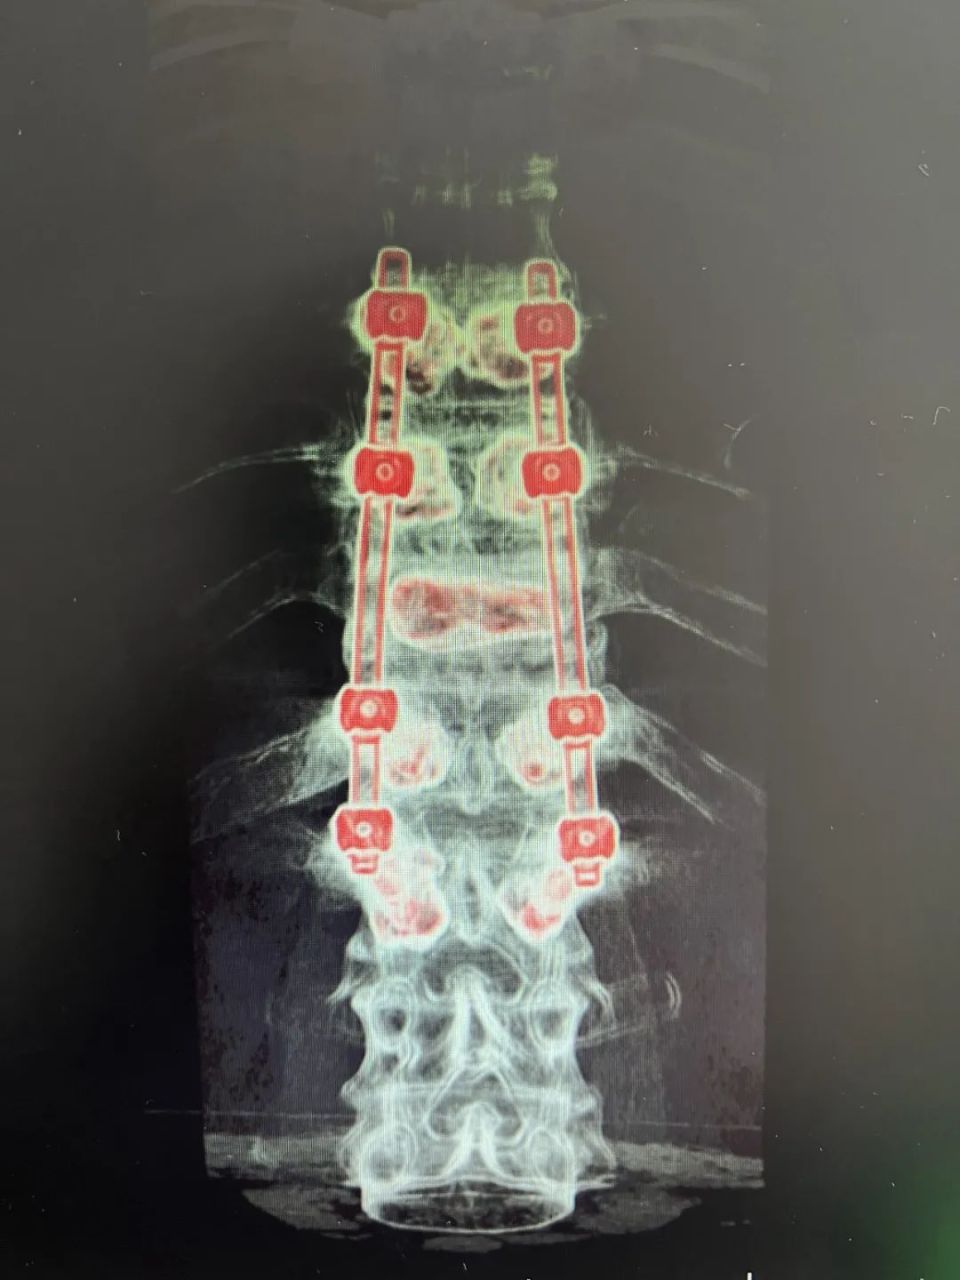

患者在神经脊柱外科诊查后发现:患者骨质疏松非常严重,1年前摔倒至胸椎骨折一直未愈合,此次摔倒进一步使胸椎压缩性骨折,继发椎管狭窄、骨髓水肿等。如任病情发展,患者很快就会瘫痪。

图片